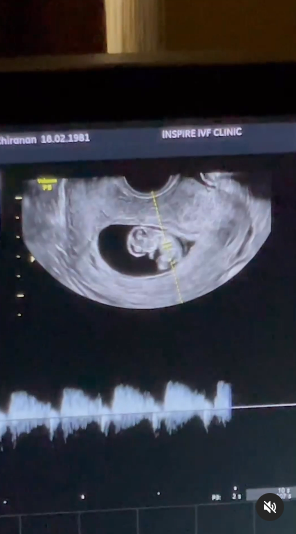

ยุ้ย จีรนันท์ เผยภาพอัลตราซาวด์ อวดโฉมลูกในท้อง แฮปปี้ลูกแข็งแรง รู้เลยซนตั้งแต่ในท้อง แววกระโดดโชว์คุณหมอไปเลย

ล่าสุด (29 กันยายน 2566) สาวยุ้ย ก็ออกมาเผยโฉมลูกน้อยในท้องผ่านคลิปภาพอัลตราซาวด์ให้แฟน ๆ ได้ติดตามเป็นครั้งแรก ซึ่งก็ต้องบอกเลยว่าหนูน้อยแข็งแรงมากแถมดูแววแล้วน่าจะซนตั้งแต่เด็ก เพราะกระโดดโชว์คุณหมอไป 1 ทีเลย

"วันนี้ หนูกระโดดโชว์พ่อกับคุณหมอด้วยนะคะ...หัวใจของหนูแข็งแรงดี แขนขาหนูมาแล้ววว รอประกอบร่างพร้อมแล้ว จะได้ออกมาเจอกันนะคะ"